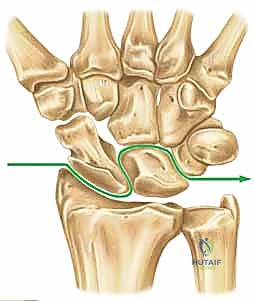

- Lesser Arc Injuries: These are purely capsuloligamentous and progress through four stages, as described by Mayfield et al.:

Figure 2A: Progression of capsuloligamentous injury in a lesser arc pattern.

- Greater Arc Injuries: These follow a similar progression but involve associated carpal fractures, commonly through the radial styloid, scaphoid, capitate, or triquetrum.

Figure 2B: Transscaphoid perilunate injury pattern, a common greater arc injury.